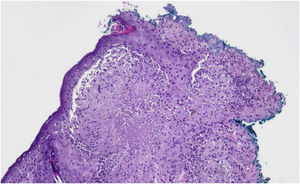

LMDF predominantly affects young adults, with a slight predominance in males, and has a self-limiting course, and may leave residual atrophic scars. Histopathologically, it shows epithelioid cell granulomas with central necrosis and surrounding lymphocytic infiltrate, including multinucleated giant cells. However, the histological pattern may vary depending on the stage of the disease.4 Due to clinical and histological similarities, LMDF can be confused with other facial granulomatous dermatoses, such as granulomatous rosacea and sarcoidosis. The presence of caseous necrosis in granulomas is a distinctive element that aids in diagnostic differentiation.5,6

Initial treatment included hydroxychloroquine on alternate days, topical pimecrolimus, moisturizers, and sunscreen. After six months, even with the addition of oral corticosteroids and topical tacrolimus, there was no significant improvement. A new biopsy was performed, with suspicion of periorificial dermatitis or LMDF. The anatomopathological examination revealed epithelioid cell granulomas, some with central caseous necrosis and lymphohistiocytic infiltrate with giant cells (Fig. 3). Tests for fungi and AFB (PAS and Fite-Faraco staining) were negative, confirming the hypothesis of LMDF.